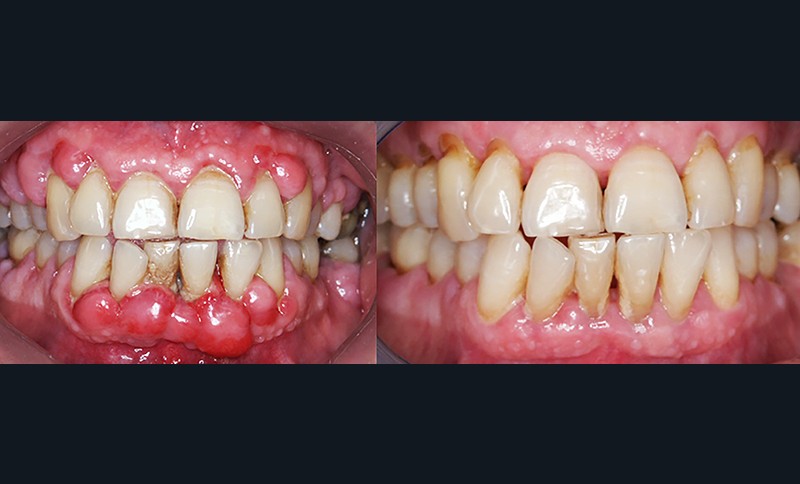

Quand et comment intervenir par voie chirurgicale ? C’est la question à laquelle Filippo Graziani tentera de répondre car, si les techniques de débridement non chirurgical ont permis de repousser les limites des indications chirurgicales, celles-ci sont encore nécessaires (fig. 3a et b). Le choix chirurgical dépend à la fois des objectifs définis initialement avec le patient et des résultats du traitement étiologique. Les séances de chirurgie peuvent être généralisées ou localisées, et faire appel aux différentes techniques d’assainissement, de résection ou d’addition, avec la possibilité de régénération tissulaire par apport de biomatériaux.

L’objectif de cette séance est d’apporter une vue actualisée, claire et précise, nécessaire au dépistage, à la motivation et aux techniques des traitements parodontaux, et de faciliter leur intégration dans l’exercice omnipratique (fig. 4, 5 et 6).